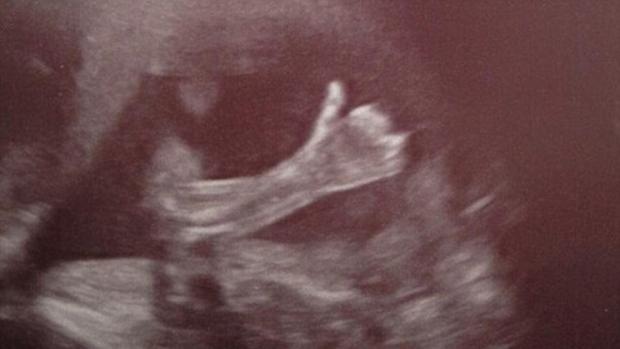

Se observă cum bebeluşul aflat încă în pântecul mamei face un semn cu mânuţa şi parcă ar confirma că totul este în ordine cu el, ridicând degetul mare.

Fericiţii părinţi sunt Cheryl Stevenson şi Paul Schofield din Marea Britanie, iar imaginea a fost surprinsă la Spitalul Saint Mary din Manchester, acolo unde medicii au rămas şi ei surprinşi.

La momentul acela, mămica se afla în cea de-a 20-a săptămână de sarcină, iar beluşul este un băieţel.